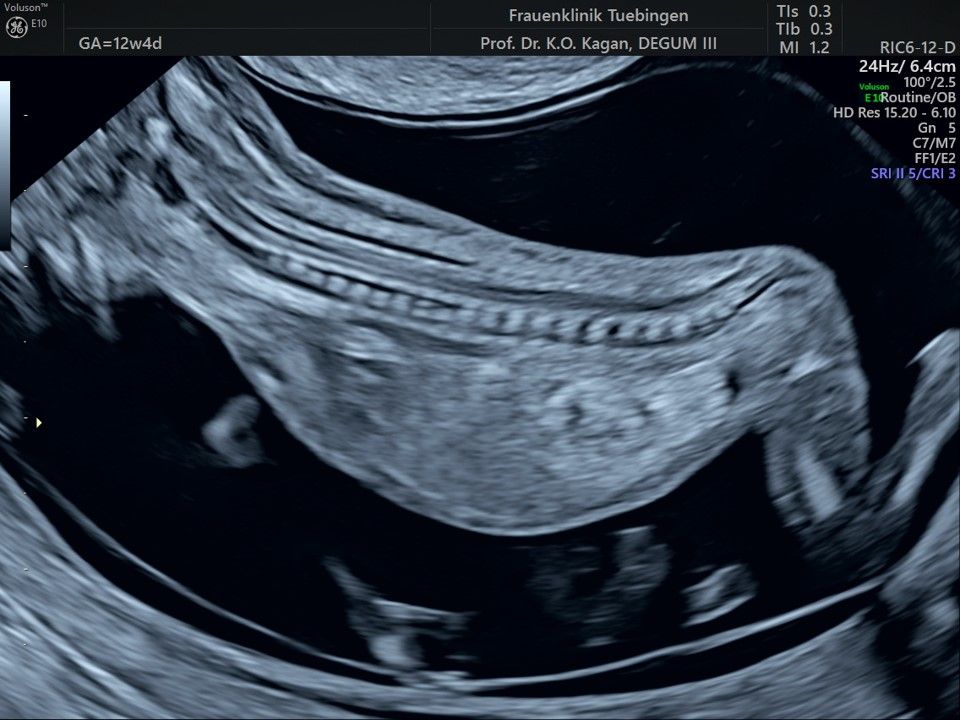

Im Rahmen des Ersttrimester-Screenings untersuchen wir die Organe des Feten mittels Ultraschall. Dabei machen wir auch gerne ein Bild für Sie.

Obwohl der Fet zu diesem Zeitpunkt erst zwischen 5 und 8cm groß ist, lassen sich bereits etwa die Hälfte aller schwerwiegenden Fehlbildungen erkennen bzw. ausschließen. Sollten wir eine Auffälligkeit sehen, werden wir mit Ihnen den Befund und das weitere Vorgehen ausführlich besprechen.

Die eigentliche Organuntersuchung findet um die 20.SSW (zweites Screening) statt. Das Ersttrimester-Screening und das zweite Screening sind sich ergänzende Untersuchungen und ersetzen sich gegenseitig nicht.

Fetale Anatomie